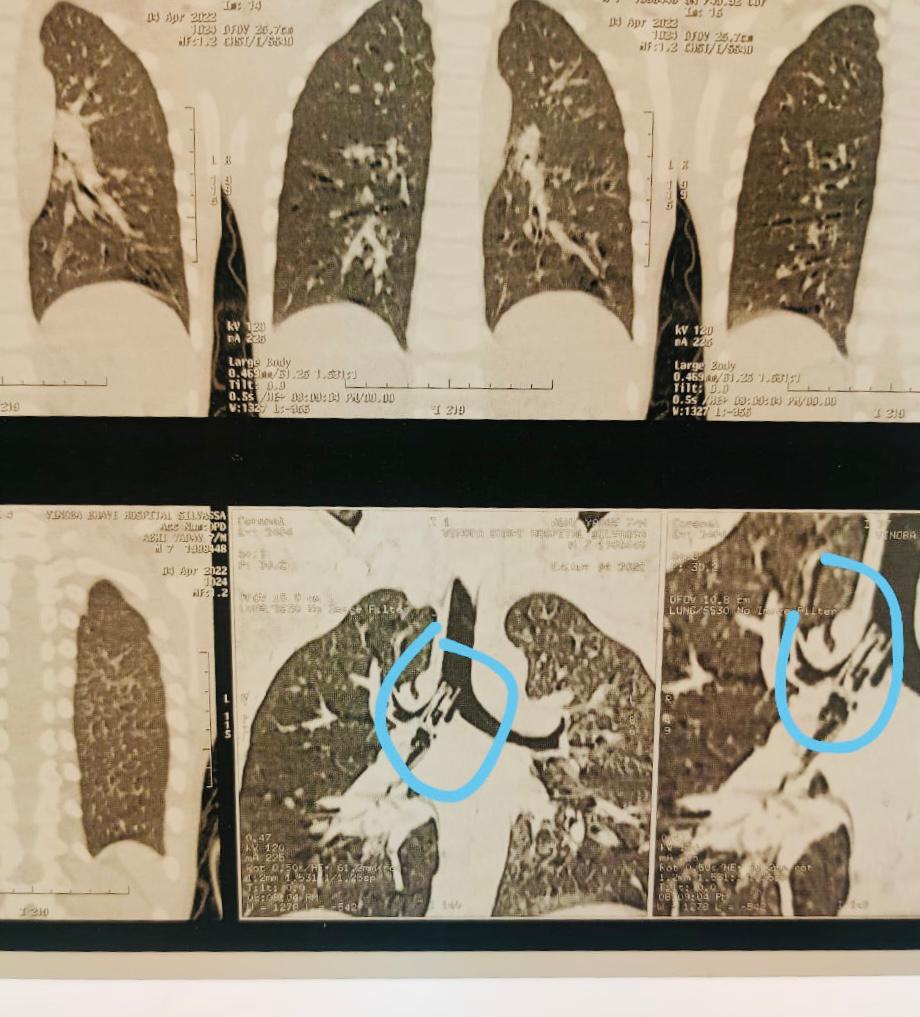

श्री विनोबा भावे सिविल अस्पताल में दिनांक 04-04-2022 के रात एक 07 वर्षीय बच्चा अशोक यादव जो की दमन का रहवासी हैं उसे लाया गया.बच्चे के परिजनो से पूछे जाने पर पता चला की बच्चे को सांस लेने में कुछ तकलीफ हो रही है और बच्चा बहोत डरा हुआ हैं,फिर यह भी बताया की इसने प्लास्टिक की सीटी 3 दिन पहले खेलते समय गलती से निगल ली हैं,जिसके बाद तुरंत ही बच्चे को दमन मरवड़ अस्पताल में ले जाया गया था और आगे की हेतु विशेषज्ञ चिकित्सको को दिखाने के लिए सिलवासा के श्री विनोबा भावे सिविल अस्पताल में भेजा गया. बच्चे के अस्पताल में आते ही ENT सर्जन एवं बच्चो के विशेषज्ञ की टीम ने जांच पड़ताल की,जिसमे प्लास्टिक की सीटी स्वास नाली से होते हुये फेफड़े के नली में फस गई थी,जिसे CT Scan एवं X-Ray में देखा जा सकता था।

यह जानकारी स्वास्थ्य निदेशक डॉ.वी.के.दास को चिकित्सको द्वारा दी गई और स्वास्थ्य निदेशक ने बिना कोई देरी किए सर्जरी की तैयारी करने के लिए सभी विशेषज्ञ चिकित्सको को जो इस बच्चे के इलाज एवं ऑपरेशन करेंगे उनके साथ सलाह – मशवरा करने के पश्चात 04/04/2022 के रात को तत्काल उसे भर्ती कर उस 7 वर्षीय बच्चे की एक कठिन bronchoscopy की गई जोकि काफी बड़ी और जोखिम भरी प्रक्रिया मानी जाती हैं। उस बच्चे के फेफड़े में प्लास्टिक के सीटी अगर फंसी रहती तो शायद उसको जान का खतरा हो सकता था।